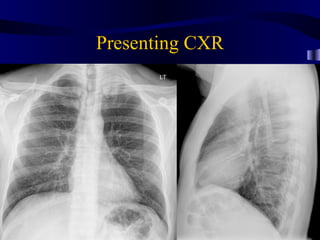

Presenting CXR

MRI Computed Tomography